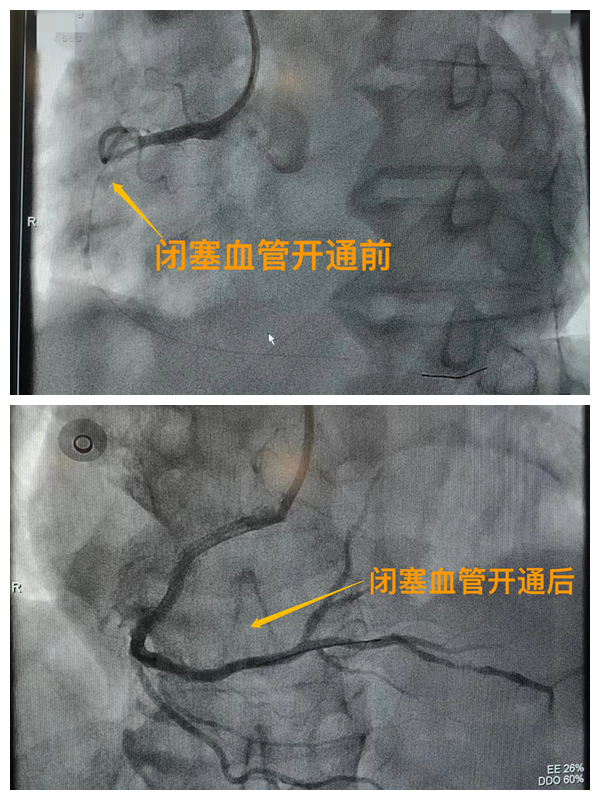

市二院胸痛中心于2021年12月23日通過(guò)中國(guó)胸痛中心認(rèn)證,成為國(guó)家級(jí)胸痛中心,先后開(kāi)展了冠心病的介入診療、心律失常的心內(nèi)電生理檢查及射頻消融治療、永久起搏器植入、先天性心臟病的介入封堵及臨時(shí)起搏器植入、主動(dòng)脈內(nèi)球囊反搏治療等,完成心臟介入手術(shù)3000余例。多次創(chuàng)造從入院至行急診介入手術(shù)開(kāi)通血管(入門(mén)-導(dǎo)絲通過(guò))30分鐘以?xún)?nèi)記錄,極大保證了患者的生命安全,提高了預(yù)后質(zhì)量,挽救了眾多急性心?;颊叩纳?span style="text-align: right;">(尹紅婭       張   靜)